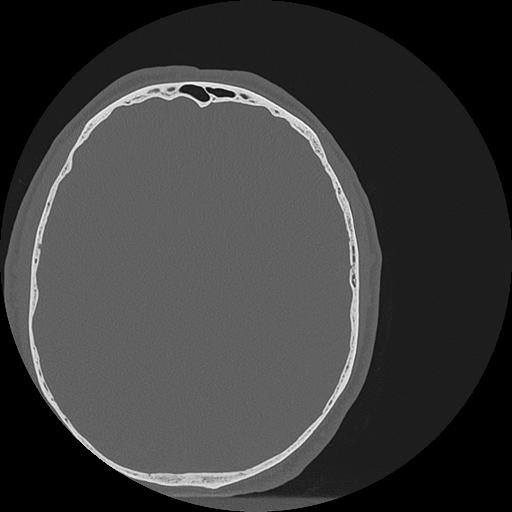

7 HUESO,,Vol,0.5,HUESO,,